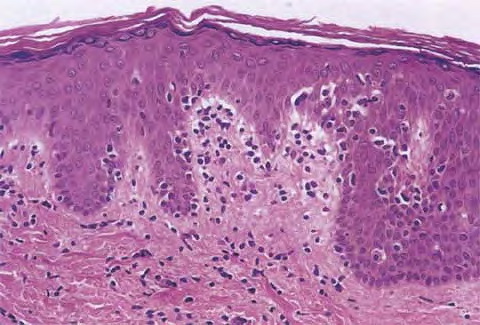

Mycosis Fongoïde =التفطر الكمئي